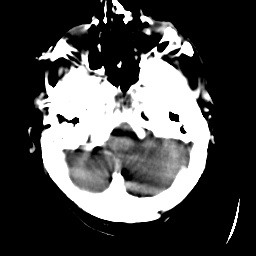

Meningioma: Roentgen-ray CT #1 -- Slice #2

[Home][Help][Clinical] Slice 2